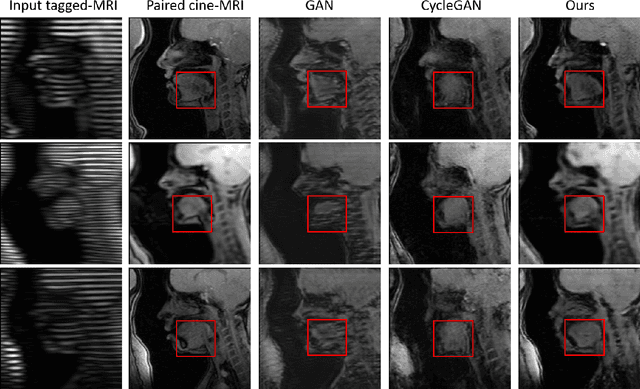

Abstract:Cycle reconstruction regularized adversarial training -- e.g., CycleGAN, DiscoGAN, and DualGAN -- has been widely used for image style transfer with unpaired training data. Several recent works, however, have shown that local distortions are frequent, and structural consistency cannot be guaranteed. Targeting this issue, prior works usually relied on additional segmentation or consistent feature extraction steps that are task-specific. To counter this, this work aims to learn a general add-on structural feature extractor, by explicitly enforcing the structural alignment between an input and its synthesized image. Specifically, we propose a novel input-output image patches self-training scheme to achieve a disentanglement of underlying anatomical structures and imaging modalities. The translator and structure encoder are updated, following an alternating training protocol. In addition, the information w.r.t. imaging modality can be eliminated with an asymmetric adversarial game. We train, validate, and test our network on 1,768, 416, and 1,560 unpaired subject-independent slices of tagged and cine magnetic resonance imaging from a total of twenty healthy subjects, respectively, demonstrating superior performance over competing methods.

Abstract:Tagged magnetic resonance imaging (MRI) is a widely used imaging technique for measuring tissue deformation in moving organs. Due to tagged MRI's intrinsic low anatomical resolution, another matching set of cine MRI with higher resolution is sometimes acquired in the same scanning session to facilitate tissue segmentation, thus adding extra time and cost. To mitigate this, in this work, we propose a novel dual-cycle constrained bijective VAE-GAN approach to carry out tagged-to-cine MR image synthesis. Our method is based on a variational autoencoder backbone with cycle reconstruction constrained adversarial training to yield accurate and realistic cine MR images given tagged MR images. Our framework has been trained, validated, and tested using 1,768, 416, and 1,560 subject-independent paired slices of tagged and cine MRI from twenty healthy subjects, respectively, demonstrating superior performance over the comparison methods. Our method can potentially be used to reduce the extra acquisition time and cost, while maintaining the same workflow for further motion analyses.